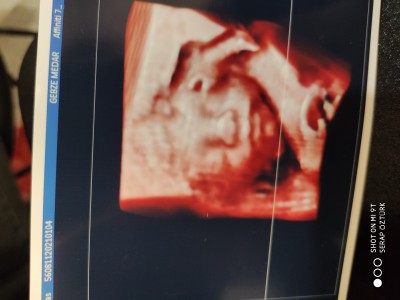

Kizlar 23+2 den herkese selamlar detaylı ultrason randevumuzu da aldık. İnşallah sağlıkla gelir

image